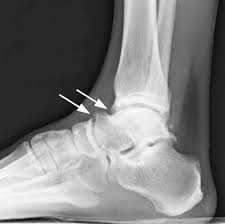

Рентгенограммы пациента с передним импиджмент синдромом

Выполняются рентгенограммы голеностопного сустава в двух проекциях. На обычных рентгенограммах остеофиты (костные шпоры) на голени или таранной кости чётко определяются. Можно выполнить боковые стресс-рентгенограммы, когда при приседании на корточки можно выявить соударение костных поверхностей в передней части голеностопного сустава, а при вставании на носки - соударение в задних структурах голеностопного сустава.

На рентгенограмме нередко можно увидеть гипертрофированный задний отросток таранной кости или os trigonum. В случаях перенесенных ранее травм мы ищем признаки несросшегося перелома в этой области.